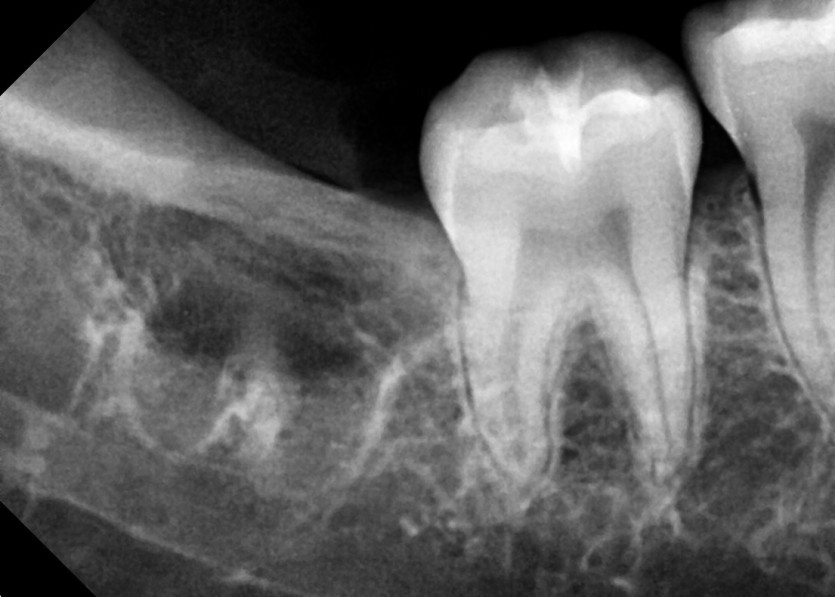

#38,48 사랑니 발치

구강 외과 전문의가 당일 발치했습니다.